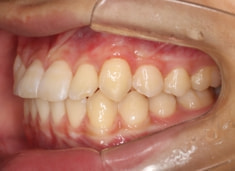

治療前